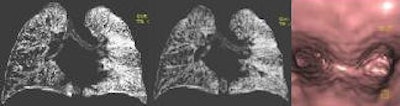

| Patient was a 24-month-old-boy hospitalized with sudden onset cough and dyspnea. Consecutive coronal VRT image shows a stenosis in the division of right intermediate and upper lobe bronchus. Also, the right lung shows hyperaeration due to air trapping (images at left and center). Virtual bronchoscopy image reveals obstruction in the right main bronchus (right). At bronchoscopy a piece of nut was removed. |